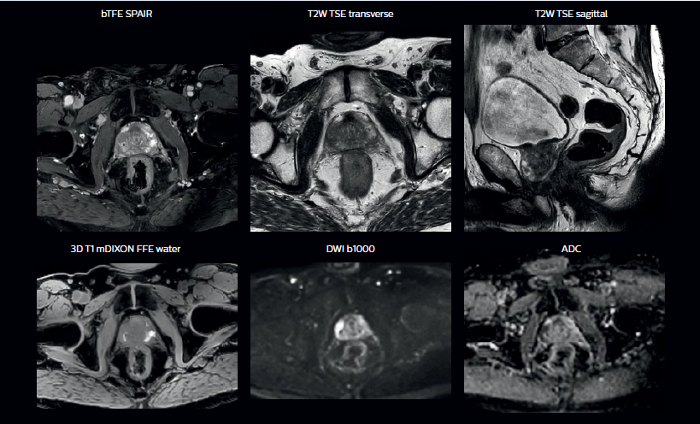

With its superior soft tissue contrast compared to CT, MRI offers exquisite visualization of tumor boundaries and proximity to nearby critical structures.

The ability to tune contrasts can provide even more valuable information about tumor characteristics and tumor extent to facilitate enhanced delineation, and also provides possibilities for dose boosting strategies.

In addition to anatomical imaging, MRI offers the ability to obtain functional information that is beneficial for tumor detection and delineation, and for response monitoring.

Diffusion-weighted imaging (DWI) for example depicts areas of high signal intensity in soft tissues that are indicative of the restricted water mobility (i.e., diffusion) of a tumor and can also be used to identify lymph nodes. Changes in the tissue’s or lesion’s apparent diffusion coefficient (ADC) can provide insights that help predict the tumor’s response to radiotherapy.